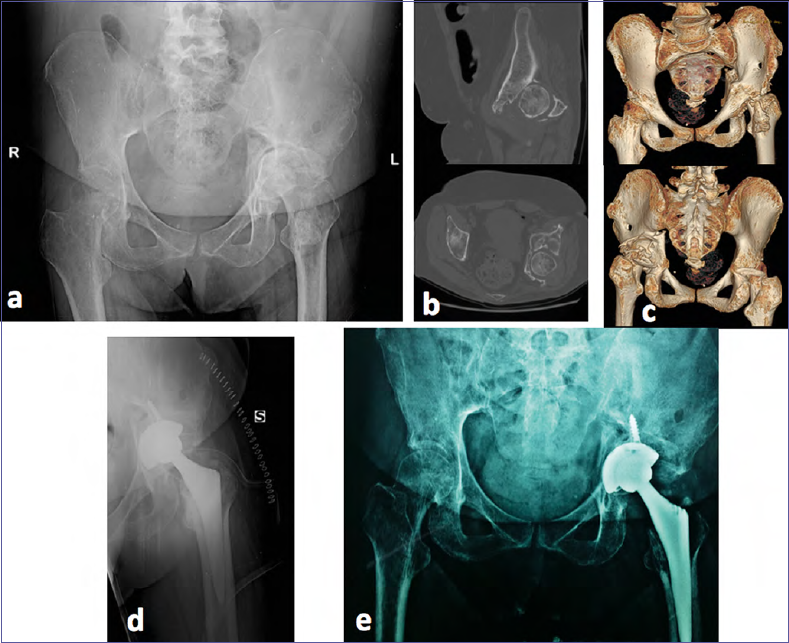

Figure 1.Example of sequeale. Inveterate acetabular fracture and dislocation of the femoral head. Poor treatment. Patient developed post-traumatic osteoarthritis (a-c). This complication is predictable and therefore modifiable. Immediate (d) and one-year (e) post-operative performed with THA.

The reduction of the femoral head dislocation, as mentioned, must take place immediately, in the emergency room (Fig. 1), except in cases where the general conditions of the patient are compromised.

The dislocation is not reduced by inserting a transfemoral traction and connecting weights, but specific reductive maneuvers are required with the patient in narcosis. It may happen that a closed reduction is impossible. This occurs in the presence of large intra-articular fragments or of a part of capsule that is interposed preventing the closed reduction. In these cases an urgency intervention must be performed if an experienced surgeon is available otherwise surgery has to be procrastinated to the following day. To leave a hip dislocated will lead, in a high percentage of cases, to necrosis of the femoral epiphysis and therefore to a negative outcome 7-10.